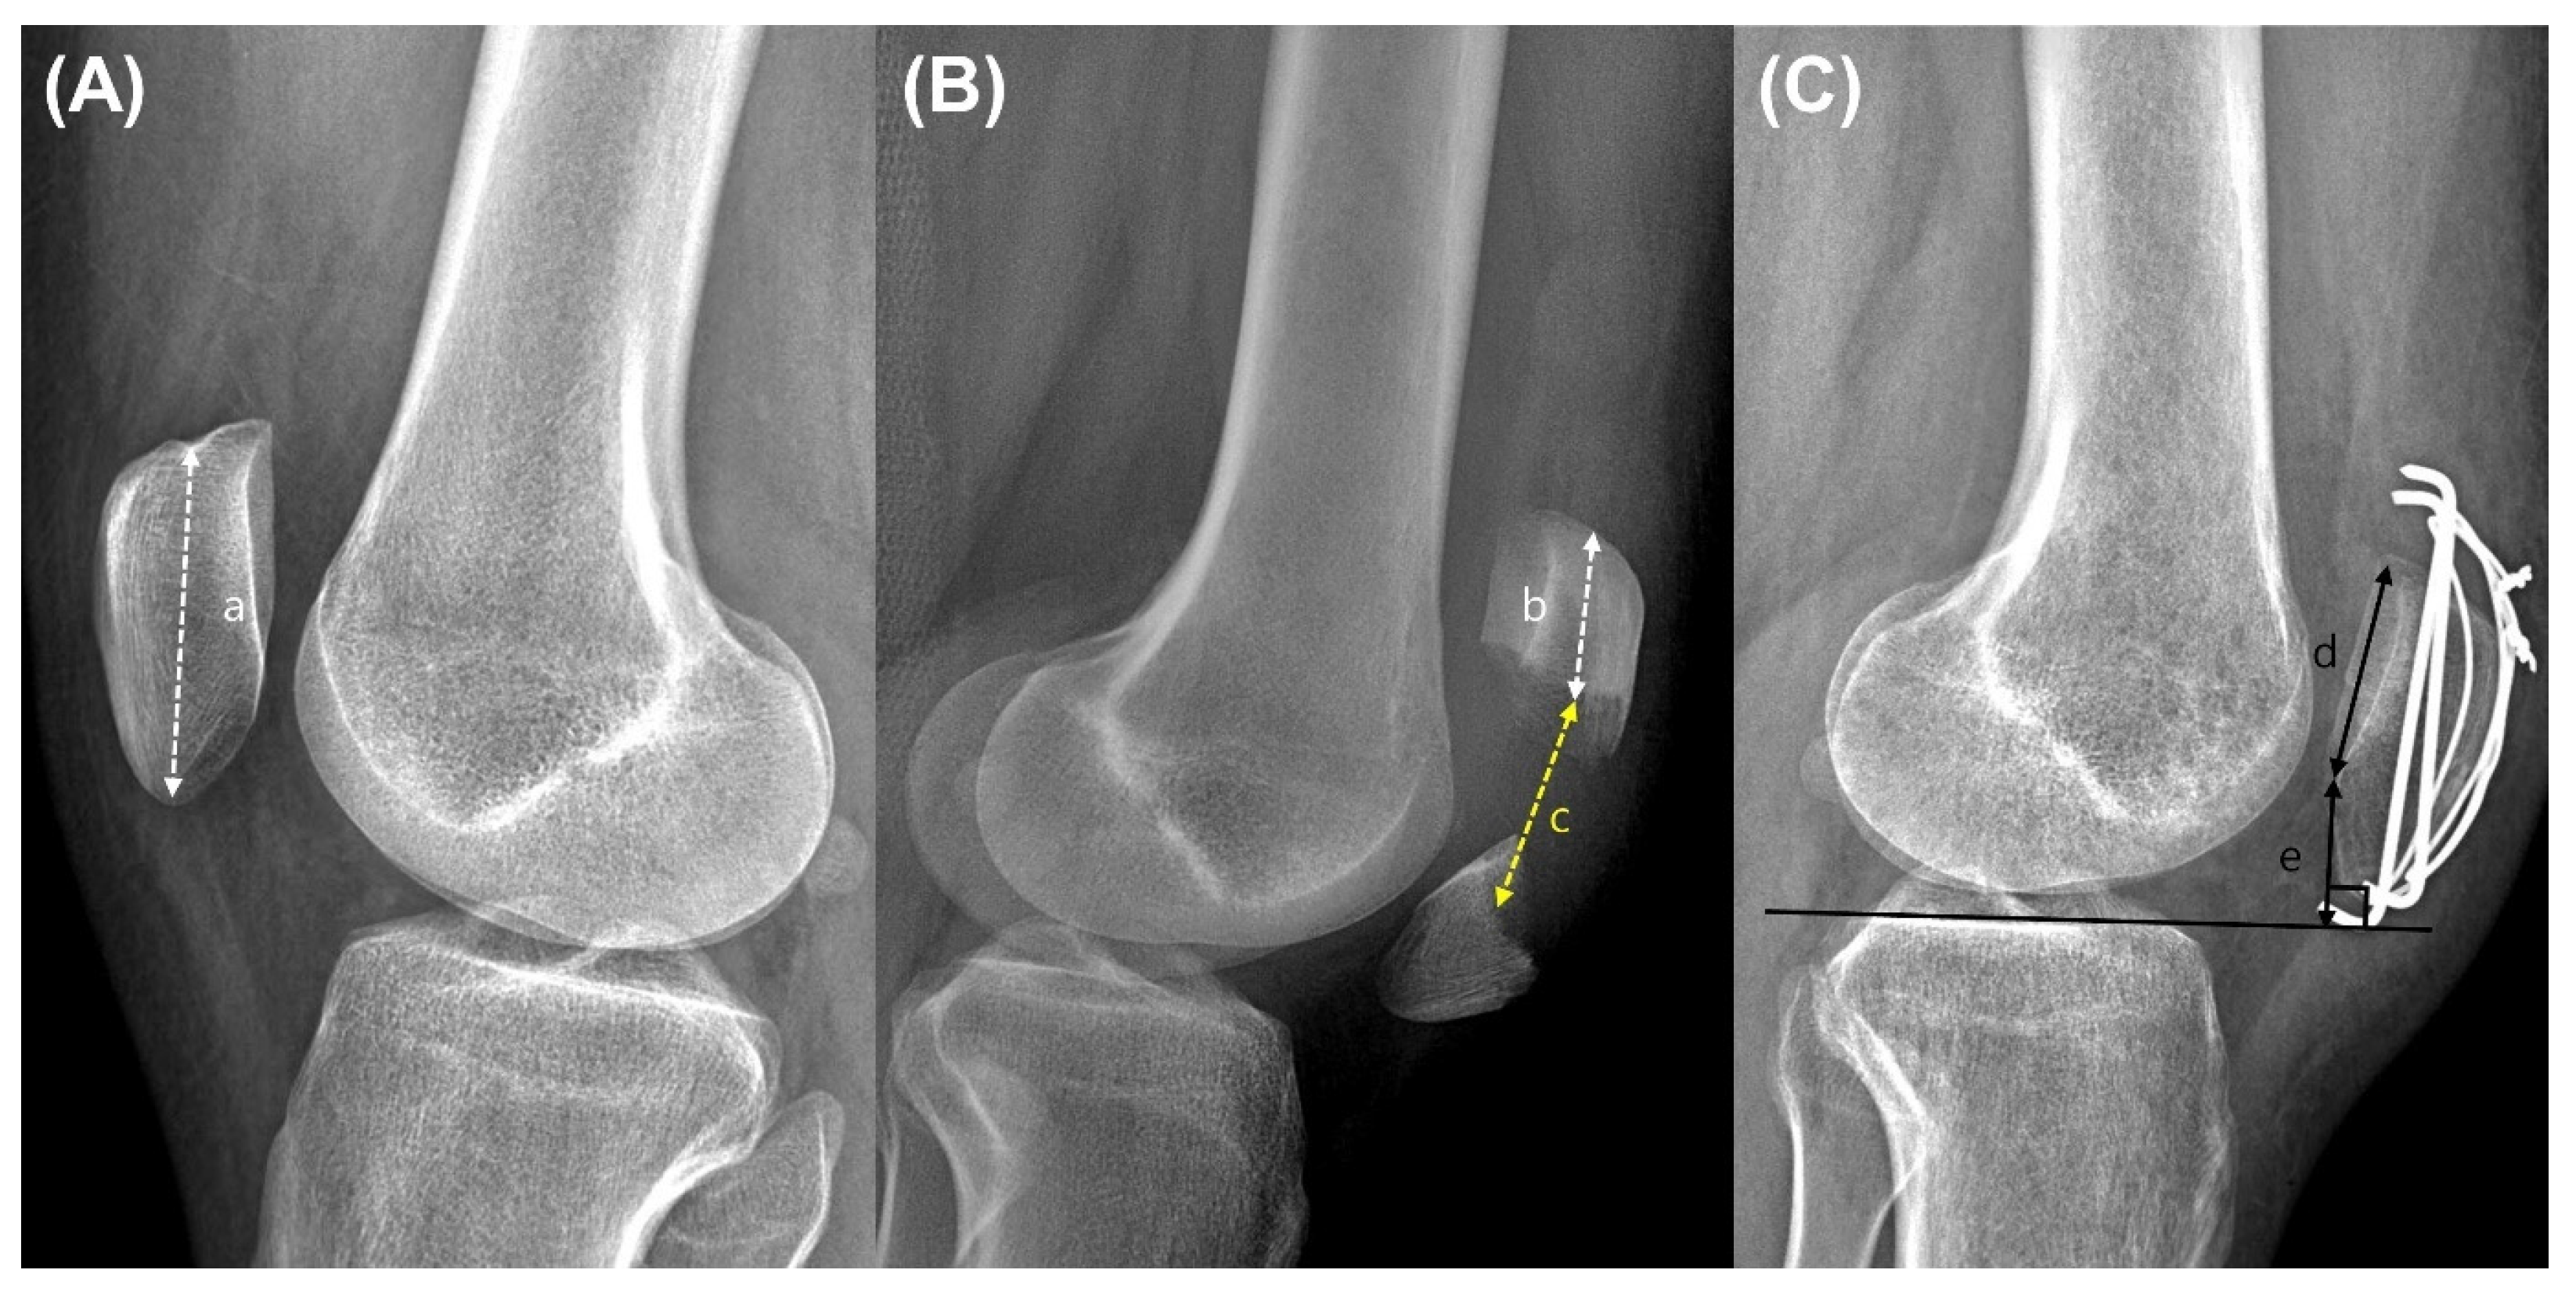

2.3. Clinical and Radiographic Assessments